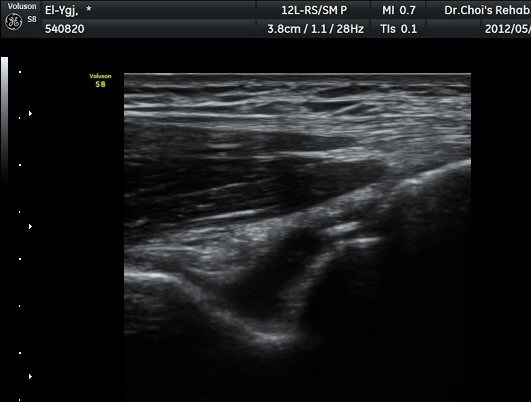

ÆÈ²ÞÄ¡ ³»Ãø Á¾´Ü¸é°ú Ⱦ´Ü¸é°Ë»ç¿¡¼­ ȰÂ÷ ¾Õ°ú °¥°í¸®µ¹±â¿Í(coronoid fossa)¿¡ ¼ö¾×Àú·ù°¡

°üÂûµÇ°í °¥°í¸®µ¹±â¿Í¿¡ °í¿¡ÄÚ »À µ¢¾î¸®°¡ °üÂûµÈ´Ù(±×¸² 2, 3).